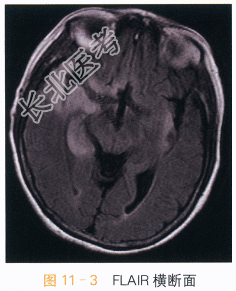

影像学资料如图11-1~图11-4所示。

读片分析:两侧岛叶及右侧颞叶可见片状异常信号影,右侧为著,呈T₁WI低信号,T₂WI、FLAIR高信号影,增强后可见轻度强化,未侵及两侧基底节区。两侧岛叶及右侧颞叶异常信号灶,右侧为著,结合患者临床表现及其它检查考虑病毒性脑炎可能。